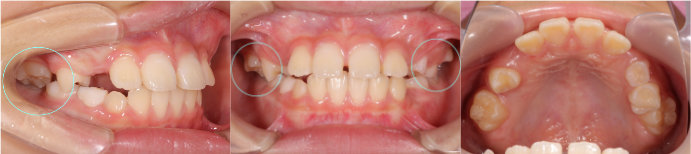

| Case4 |

| 前歯のガタガタ |

| <治療前> |

| <治療後> |

| 主訴 |

上の前歯がガタガタしている |

| 診断名 |

上顎前歯の重度の叢生、下顎前歯の中程度の叢生 |

| 年齢 |

8歳 |

| 使用装置 |

マルチブラケット装置 |

| 抜歯部位 |

永久歯の抜歯は無し |

| 治療期間 |

3年9か月 |

| 治療費概算 |

検査・診断料:5万円+税 装置・技術料:25万円+税 おおよそ1か月ごとの処置・管理料:5,000円+税 保定装置料:5万円+税 |

| リスク・副作用 |

う蝕 |